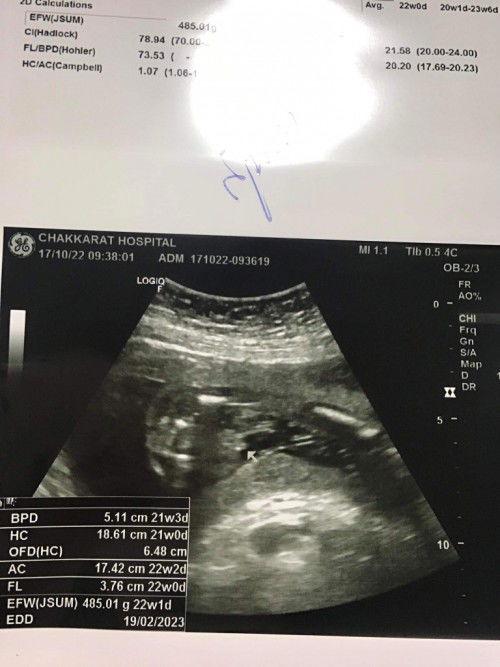

น้องจู๋รึป่าวคะ ผู้ชายแน่เลยย

เหมือนจู๋ลูกชายบ้านนี้เลยค่ะ

ผู้ชายแน่เลยค่ะแม่

ชายค่ะแม่

จู๋ๆๆจร้า

ชายจ้า